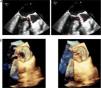

Infectious parameters began to decrease over the initial days of antibiotic treatment. Two-dimensional (2D) and three-dimensional (3D) TTE and transesophageal echocardiography (TEE) showed absence of endocarditis progression and an apparently unaffected, normal-functioning aortic prosthesis, with similar findings as in the initial echocardiography (Figure 1).

Consequently, repeat 2D and 3D TTE and TEE revealed a previously non-existent, or not visible, 5-6 mm vegetation (Figure 3 and Supplementary Video 1). The vegetation was observed on the posterior surface of the aortic prosthesis and was not causing regurgitation. A nodule persisted on the anterior surface of the mitral valve, but the positron emission tomography/computed tomography (PET/CT) images showed it to be only a simple degenerative finding. No abscesses or other complications of IE were observed and the mechanical aortic prosthesis discs were opening normally, with a mean gradient of 25 mmHg and no significant regurgitation.

(A) 2-dimensional and (B) 3-dimensional transesophageal echocardiography. A 5-6 mm vegetation can be seen on the posterior surface of the aortic prosthesis, with a nodule persisting on the anterior surface of the mitral valve. No abscesses or other complications of infective endocarditis are observed and the mechanical aortic prosthesis discs are opening normally.